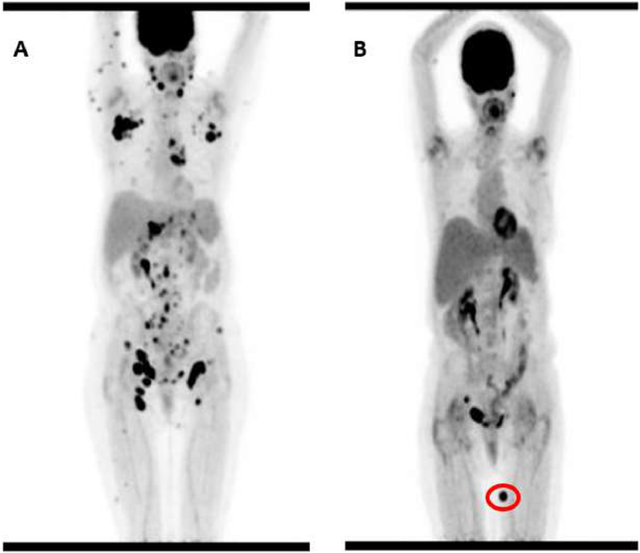

2020年3月,贝勒医学院细胞和基因治疗中心研究人员描述了一项针对复发或难治性(r/r)T细胞恶性肿瘤的自体CD5靶向CAR-T细胞的I期剂量递增研究(NCT03081910)。

CD5是一种泛T细胞标志物,存在于约85%的T细胞恶性肿瘤中。该研究旨在评估CD5 CAR-T细胞对r/r T细胞恶性肿瘤患者的安全性和可行性,作为桥接至异基因造血干细胞移植(allo-HSCT)的手段。

治疗了5例CD5阳性复发或难治性非霍奇金T细胞淋巴瘤(T-NHL)患者,1例血管免疫母细胞性T细胞淋巴瘤(AITL)患者和1例外周T细胞淋巴瘤(PTCL)患者获得完全缓解(CR)。

另1例广泛型AITL患者因出现新的PET阳性病灶(尽管其余病灶消退)被归类为混合反应。该患者接受了第二次CAR-T细胞输注,随后进行了造血干细胞移植,移植后6个月仍保持完全缓解。

这些结果表明,CD5 CAR-T细胞具有安全性,可在经过大量预处理的复发或难治性(r/r)T细胞恶性肿瘤患者中诱导临床反应。